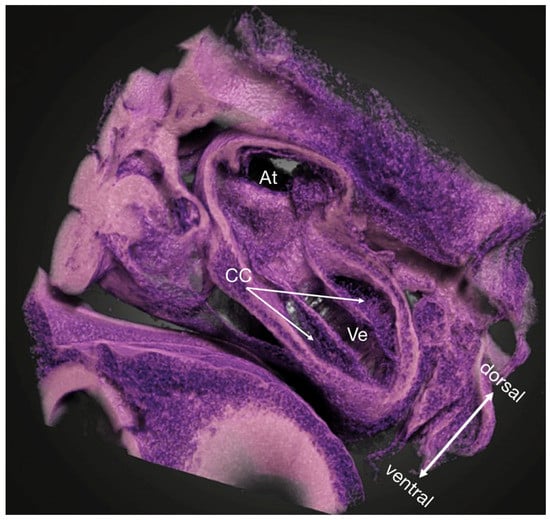

3.1. Embryo Preparation

3.2. Image Registration

3.3. Other Findings and Considerations